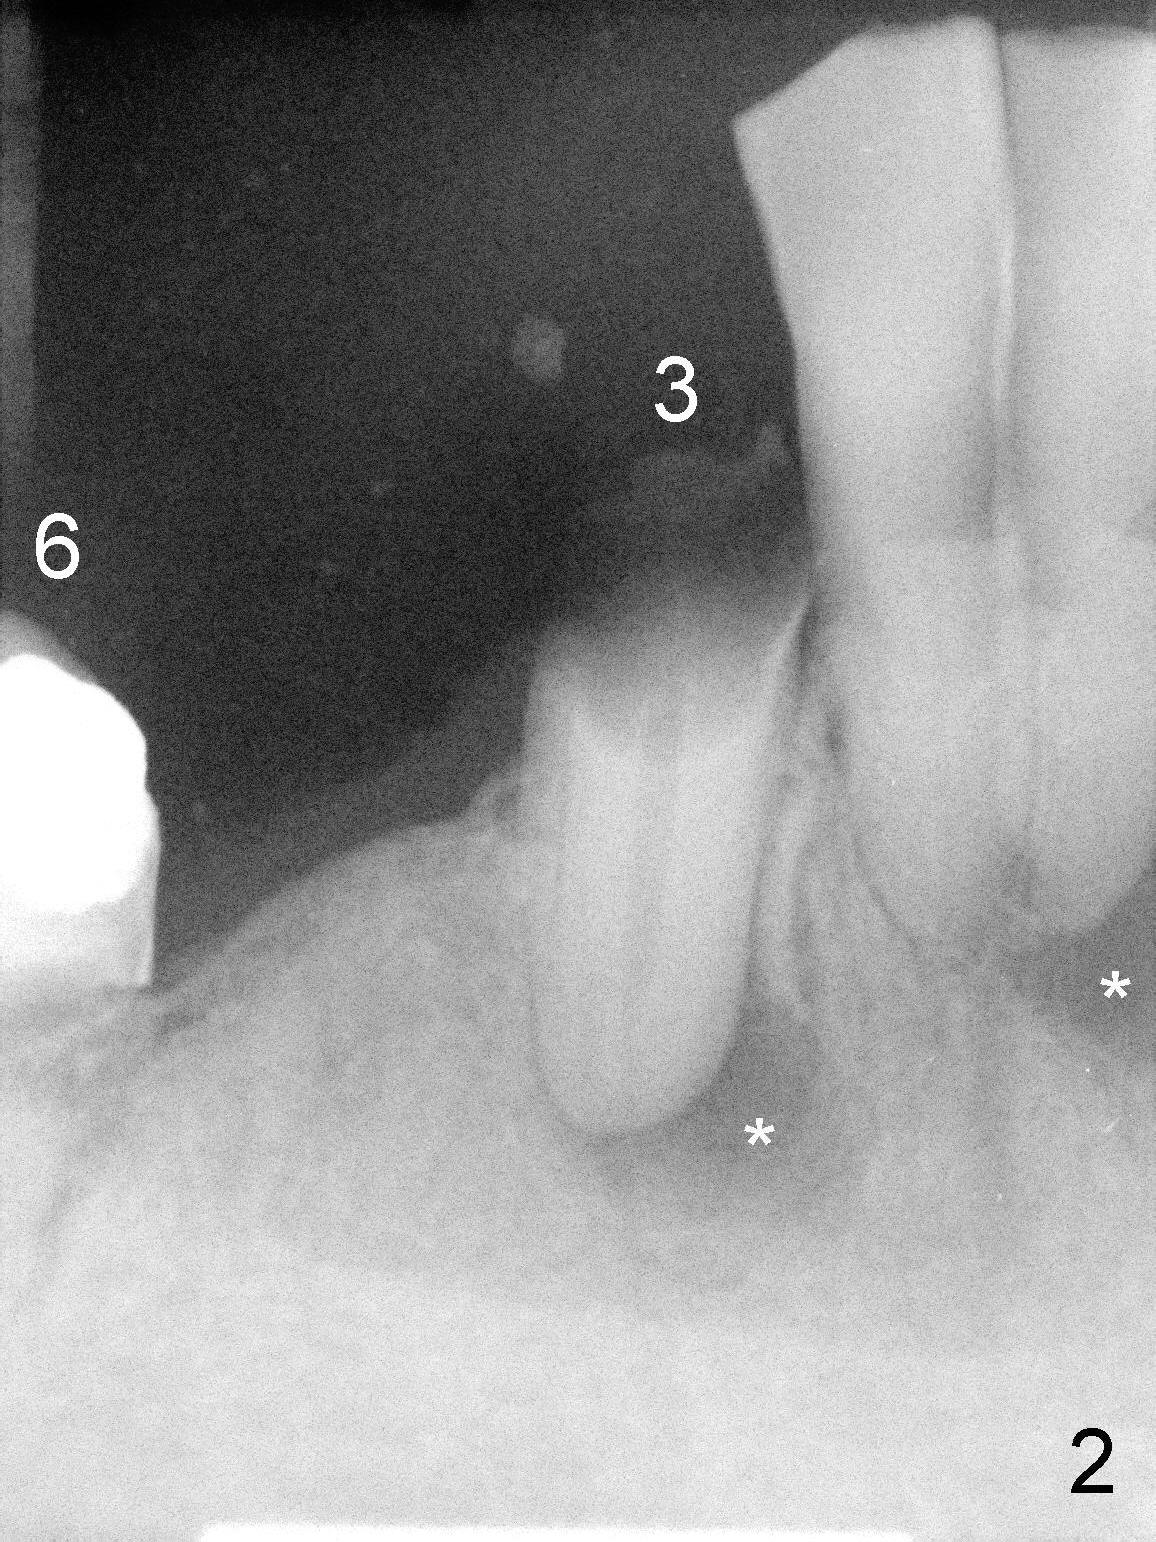

The lower right bridge (from canine (Fig.2: 3) to 1st molar (Fig.1: 6)) fails while a 77-year-old man is undergoing chemotherapy for urinary bladder cancer. The abutments of the bridge are extracted without plan for implants (Fig.4). Four months later, the patient returns for implants (Fig.3), but the ridge is narrow (Fig.5). While 2 of 3x14 mm 1-piece implant are placed at the canine and 1st bicuspid sites, 2 piece ones at the 2nd bicuspid and 1st molar sites (Fig.6: 3.5x11 mm, 5x14 mm). Soft (Fig.7-10) and hard (Fig.11) tissues heal 1 week (Fig.7) and 4 months (Fig.8-11). There is minimal bone resorption 1 year 7 months post cementation (Fig.12,13, non-splinting). It appears that narrow diameter implants are a valid solution to narrow ridge at the sites of the lower canine and premolar. As long as there are enough implants for function, the crowns are not necessary to be splinted. Surprisingly, the patient starts flossing after implant restoration. Retrospectively an immediate provisional bridge should have been fabricated.